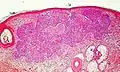

- Superficial basal-cell carcinoma, formerly referred to in-situ basal-cell carcinoma, is characterized by a superficial proliferation of neoplastic basal-cells. This tumor is generally responsive to topic chemotherapy, such as imiquimod, or fluorouracil.

| Superficial basal-cell carcinoma (also known as "superficial multicentric basal-cell carcinoma") | Occurs most commonly on the trunk and appears as an erythematous patch.[19]: 748 [2] | ![]() | |